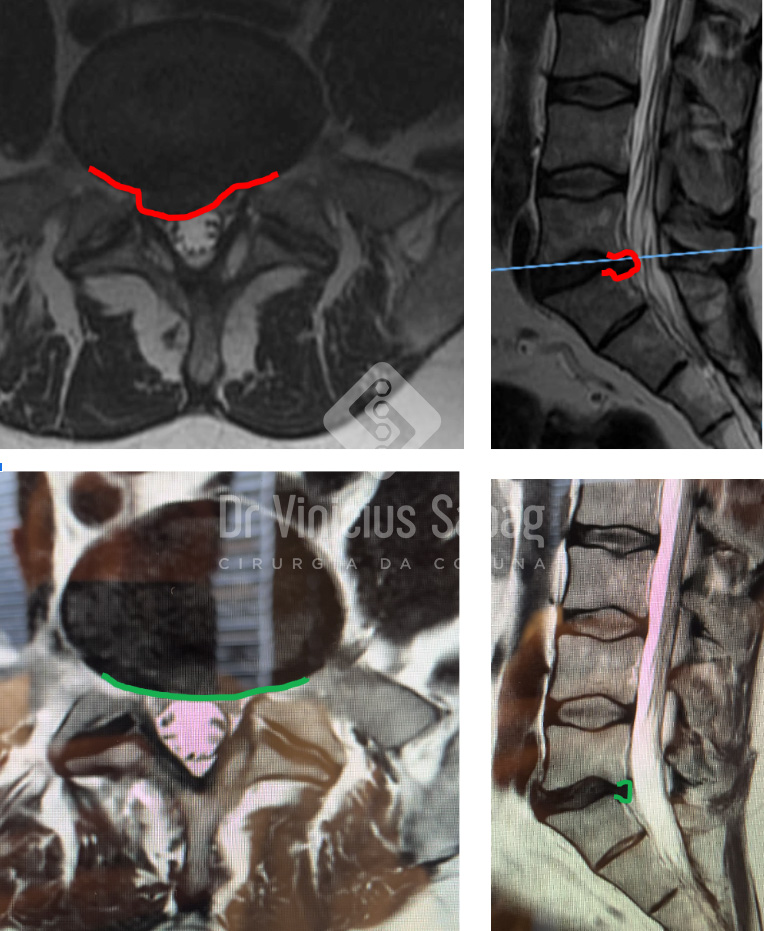

Uma nova ressonância lombar de controle evidenciou retirada completa da hérnia discal e estruturas nervosas totalmente descomprimidas, confirmando o sucesso do procedimento.

Comparativo entre as ressonâncias pré (acima) e pós (abaixo) cirurgia.